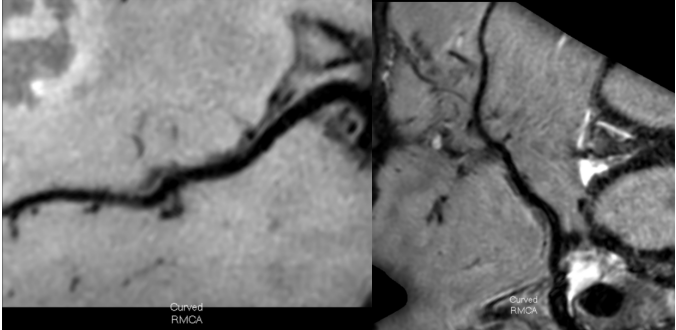

以上4图平扫的T1W-VISTAT2WT1W-3D-SNAP都发现大脑中动脉M1段的大小为1.2*1.5*2.8mm等低信号斑块。

6c7180e7ed935be81a1d0dac685b2bb3.pngf8d20e7e820aa9111b30f3e48b62d51c.png

上图是打药后扫描的T1W-VISTA+C图像,斑块表现为轻度强化,综合考虑为不稳定斑块。这种情况需要慎重处理,斑块破裂和脱落风险比较大,建议经药物治疗后随访复查。